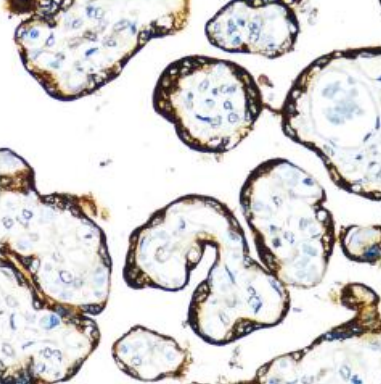

The Medikbio Anti-FGFR2 Antibody (1–100) – Catalog No. MDB23658 is a high-quality rabbit polyclonal antibody developed to detect Fibroblast Growth Factor Receptor 2 (FGFR2), a critical receptor tyrosine kinase involved in cell proliferation, differentiation, angiogenesis, and cancer progression. Designed for optimal performance in Immunohistochemistry (IHC), this antibody provides strong, clear staining with minimal background, enabling precise FGFR2 localization in both human and animal tissues.

Produced using a synthetic peptide corresponding to amino acids 1–100 of human FGFR2, the antibody demonstrates high specificity and robust reactivity with Human, Mouse, and Rat samples—making it ideal for studies involving oncology, developmental biology, and molecular signaling. Affinity purification ensures superior binding performance and reliable IHC detection, even in complex tissue environments.

FGFR2 dysregulation is widely implicated in diseases such as breast cancer, gastric cancer, endometrial cancer, craniosynostosis syndromes, skeletal abnormalities, and developmental disorders. This antibody provides researchers with a powerful tool for mapping FGFR2 expression patterns and investigating receptor-mediated pathways across various biological and pathological models.